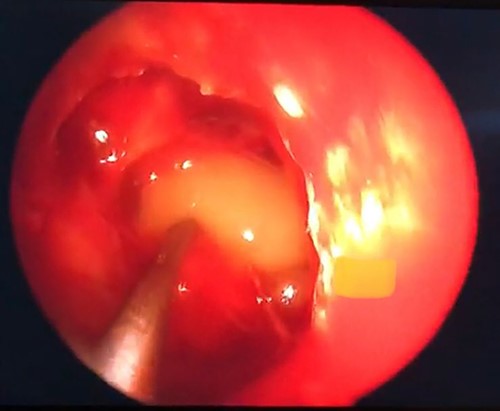

An endoscopic endonasal approach with neuronavigation through an ethmoidal approach was performed 8 days after arrival by an experienced neurosurgeon. The expanding ACP was drilled, allowing the exposure of a soft, grayish lesion consistent with mucocele (Fig. 3), which was resected and sent to pathology. A wide osteotomy of the posterior ethmoidal cell and ACP was done to allow the optic nerve decompression.

Grayish soft tissue lesion occupying the right ACP consistent with mucocele.